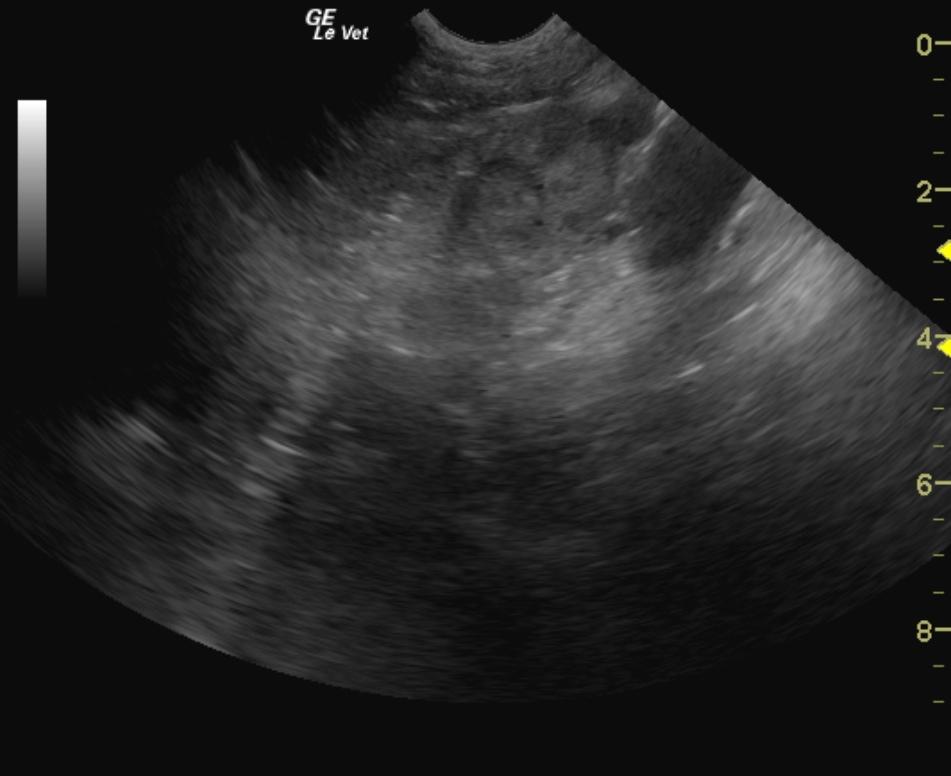

A 9 year old FS Labrador was presented for anorexia. Previous laboratory work had shown an inappropriate urine SG, 3+ proteinuria, microalbuminuria, azotemia, thrombocytosis, and negative 4Dx. The only significant abnormality on physical examination was dehydration. Baseline androstenedione and estradiol were elevated and ACTH stimulation revealed elevated cortisol, elevated estradiol, and elevated progesterone.